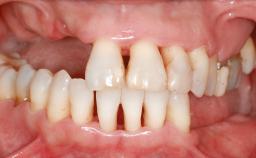

A 45-year-old woman with a completely edentulous maxilla was referred to evaluate the possibility of rehabilitation with an implant-supported prosthesis. This patient was healthy and a non-smoker. She had been wearing a maxillary complete denture opposing a natural mandibular dentition since her twenties. This situation had resulted in progressive resorption of the alveolar ridge, repeatedly creating a need for relining the denture. Twenty years later, despite multiple adaptations and the use of “glues” the denture was unstable and causing the patient psychological and functional discomfort.

Defining Characteristics Fully edentulous upper jaw to be rehabilitated with an implant-borne fixed dental prosthesis